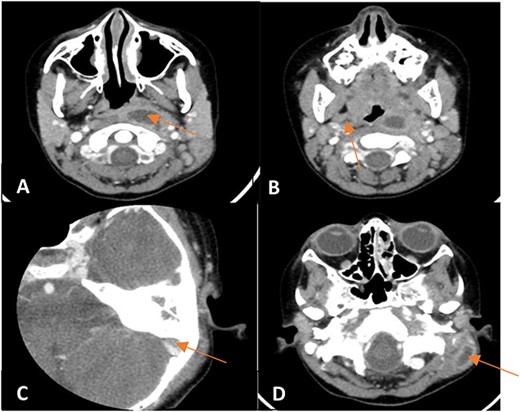

An 8-year-old female patient presented with recurrent episodes of acute otitis media (AOM) and foul-smelling yellowish discharge from the left ear with hearing loss, after receiving multiple courses of antibiotics with only slight improvement. Otoscopic examination showed left small central perforation with minimal granulation tissue and right middle ear effusion. The patient was afebrile with no constitutional symptoms. A CT scan of the temporal bone revealed signs of bilateral mastoid and middle ear opacification with left mastoid cortical erosion, an overlying soft tissue swelling, and a parapharyngeal hypodense collection that likely represents an abscess (Fig. 1). Therefore, the patient was hospitalized for further investigations.

Non-enhanced axial CT scan of temporal bone showing bony remodeling suggestive of chronic otomastoiditis.